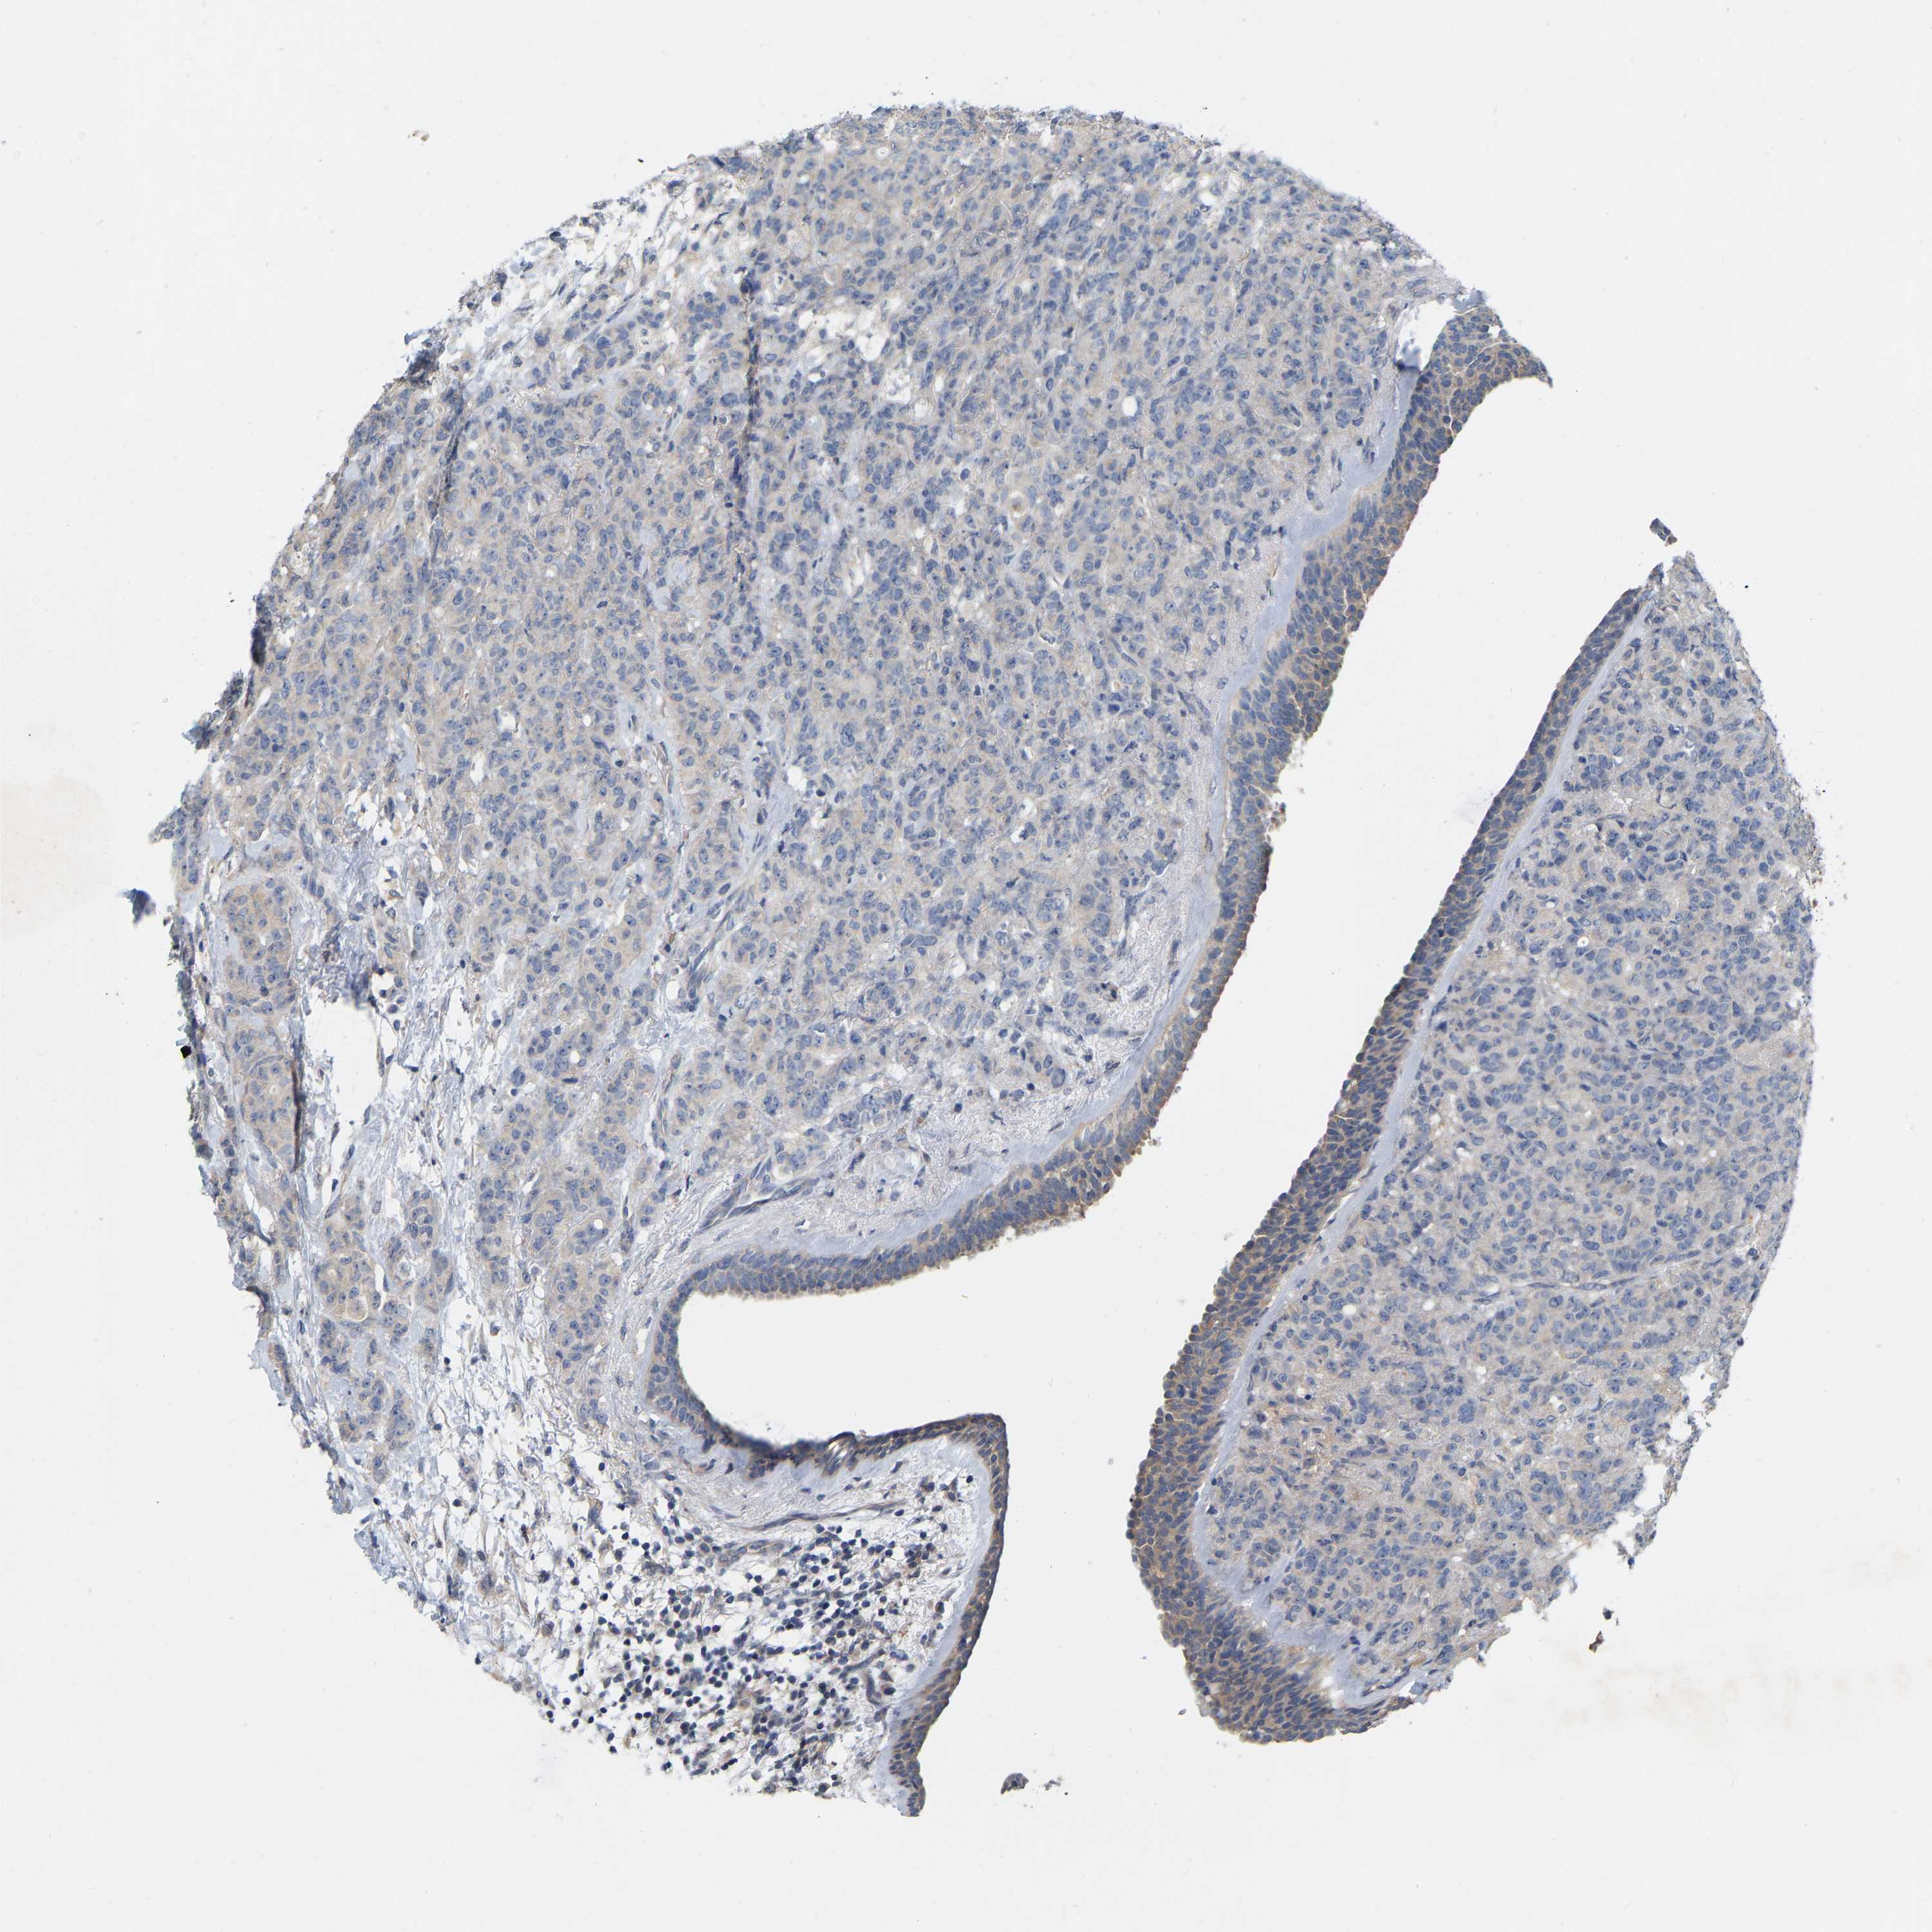

CANCER BREAST CANCER Show tissue menu

BRCA TCGA BRCA VALIDATION PROTEIN EXPRESSION

ANTIBODIES

AND

VALIDATION